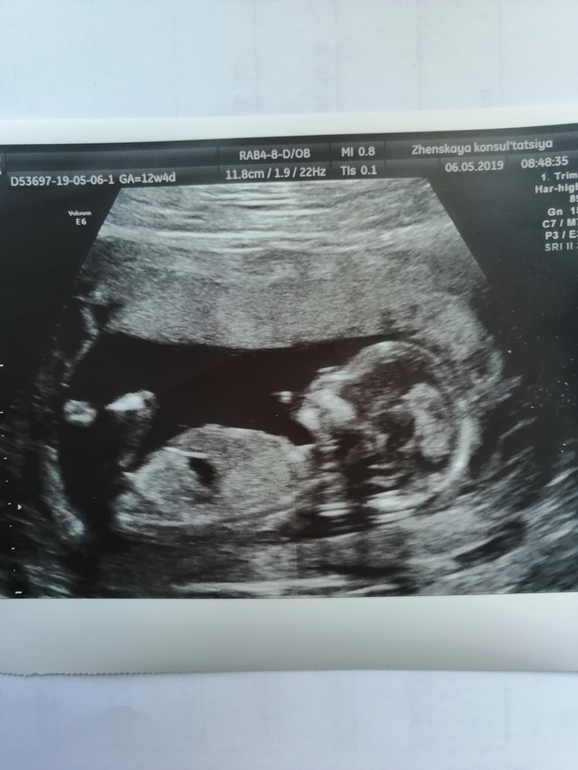

Узи 14 нед))

Девочки кто в этом деле разбирается))) Как вы думаете кто на фото мальчик или девочка?)))

Да очень долгожданное чудо))) 5 лет ждали))) Я афигел что в 14 недель он такой уже прям человечек, такой родной🤗🤗🤗

Пока просто ребенок. В том месте все закрыто ногами. Но тут конечно может по другим частям тела уже научились определять....